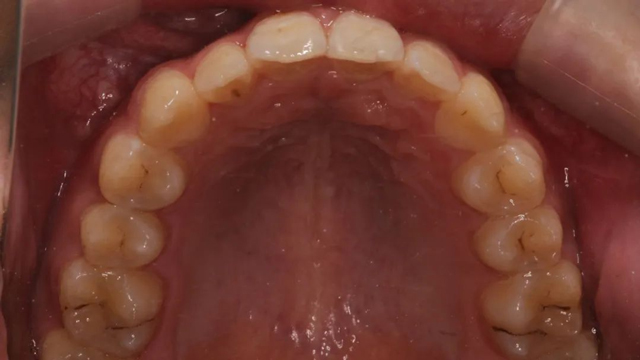

2021年8月(矫正前口内照)

这位小患者的口腔问题包括:牙列不齐,个别门牙反颌,左上尖牙完全埋伏阻生,另外,CBCT显示右上门牙牙根腭侧内还有一颗多生牙。

2024年9月(矫正结束后口内照)